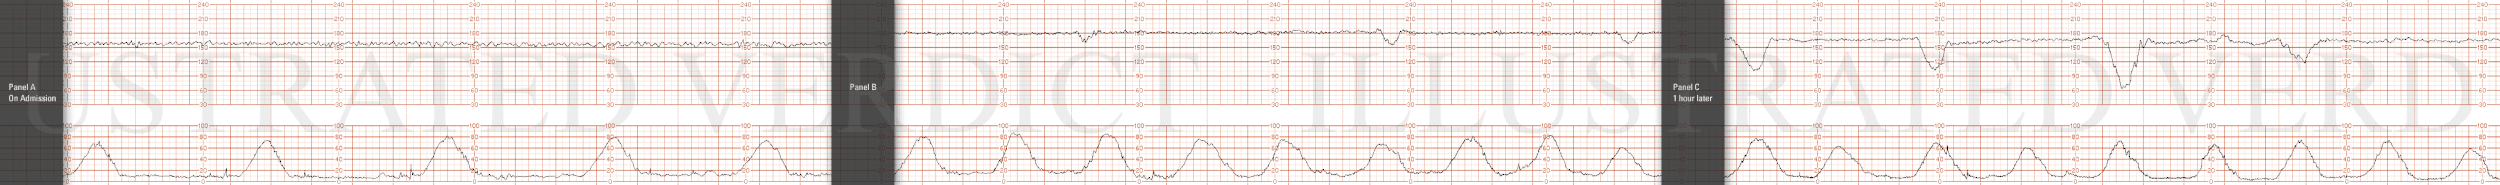

STRIP 74

1. 1st and 2nd panel:

Ctxs 8 in 18 or 9 in 20 min, each 60 sec

Baseline 180 bpm with minimal variability at 2-3 bpm

Decels – 30 second variable decels to 160, 155, 160 bpm nadir each with prompt return to baseline with one of three contractions

Accels- None

3rd panel:

Ctxs -8 in 18 or 9 in 20 mins, each 60 seconds

Baseline – 165 bpm w minimum variability at 3-4 bpm

Decels – 30 sec variable decels to 140,145,150,145 bpm (3rd decel more abrupt) nadirs, each with prompt return to baseline with one for each two-three contractions

Accels2 - None